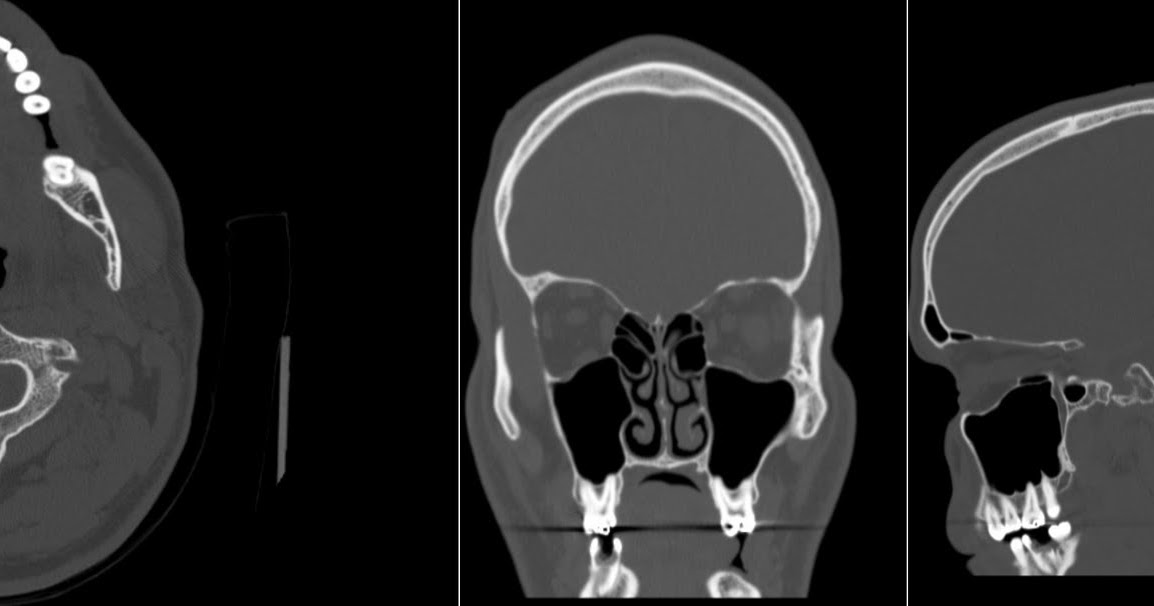

From radiologymri.blogspot.com

Radiology MRI Dental Caries on CT Old Tooth Fillings And Mri crowns made of porcelain, composite resin, or gold pose no risks from mri. If you have detachable metal braces or a retainer, you. knowledge about the interaction of dental materials and mri is essential for dentists and radiologists. magnetic resonance imaging safety concerns related to dental fillings highlight the importance of proactive. The age of a crown. Old Tooth Fillings And Mri.